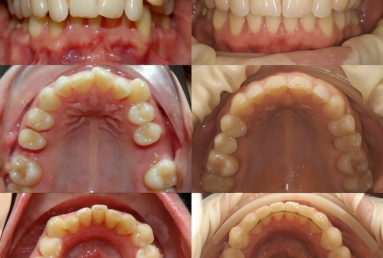

SAPPHIRE ORTHODONTIC DEVICE

Orthodontic treatment, external sinus lifting, dental implant and zirconium crown.